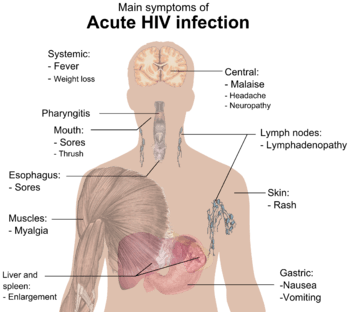

Signs and symptoms of HIV/AIDS

The stages of HIV infection are acute infection (also known as primary infection), latency and AIDS. Acute infection lasts for several weeks and may include symptoms such as fever, swollen lymph nodes, inflammation of the throat, rash, muscle pain, malaise, and mouth and esophageal sores. The latency stage involves few or no symptoms and can last anywhere from two weeks to twenty years or more, depending on the individual. AIDS, the final stage of HIV infection, is defined by low CD4+ T cell counts (fewer than 200 per microliter), various opportunistic infections, cancers and other conditions.

Acute HIV infection, primary HIV infection or acute seroconversion syndrome[2]:416) is the second stage of HIV infection. It occurs after the incubation stage, before the latency stage and the potential AIDS succeeding the latency stage.

During this period (usually days to weeks post-exposure) fifty to ninety percent of infected individuals develop an influenza or mononucleosis-like illness called acute HIV infection (or HIV prodrome),[3][4] the most common symptoms of which may include fever, lymphadenopathy, pharyngitis, rash, myalgia, malaise, mouth and esophageal sores, and may also include, but less commonly, headache, nausea and vomiting, rash, fatigue, ulcers in the mouth or on the genitals, enlarged liver/spleen, weight loss, thrush, night sweats and diarrhea and neurological symptoms. Infected individuals may experience all, some, or none of these symptoms.[5] The duration of symptoms varies, averaging 28 days and usually lasts at least a week.[6]

Because of the nonspecific nature of these symptoms, they are often not recognized as signs of HIV infection. Even if patients go to their doctors or a hospital, they will often be misdiagnosed as having one of the more common infectious diseases with the same symptoms. As a consequence, these primary symptoms are not used to diagnose HIV infection, as they do not develop in all cases and because many are caused by other more common diseases. However, recognizing the syndrome can be important because the patient is much more infectious during this period.[1]